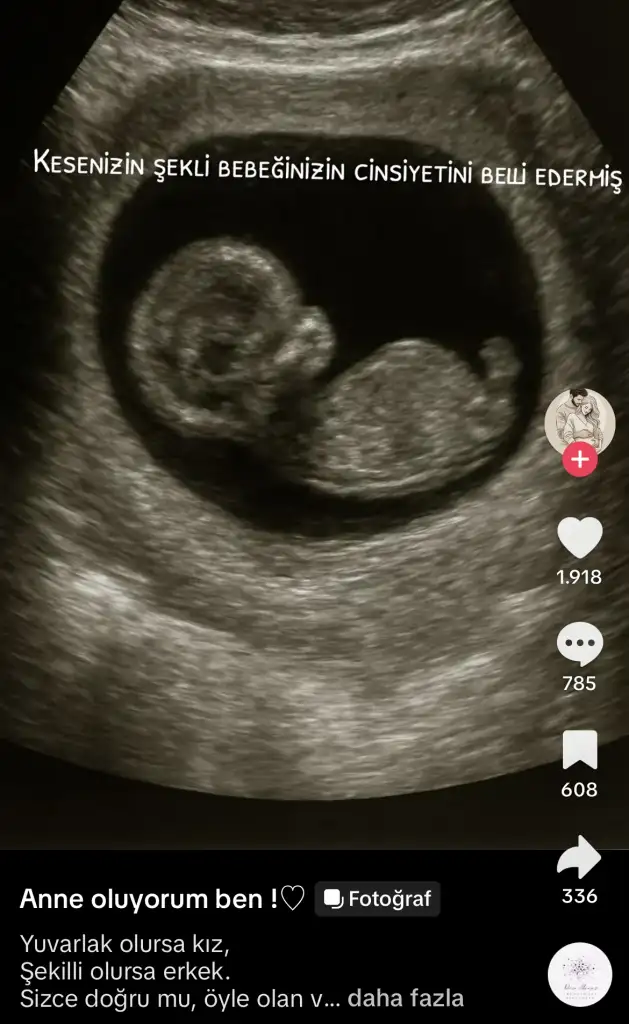

Eki Görüntüle 3637537

Şimdi tiktokta bu görseli gördüm sanki senin kesen de yuvarlak ayyy kız bebiş mi geliyor acaba![]()

Hahshsh yaaa hadi bakalım bi 6-7 haftaya öğreniriz burada cinsiyetleriYaaaa deme öyle valla içimm gidiyor kızlara ama tabiki sağlıklı olsun önemli olan o diyor dilim![]()